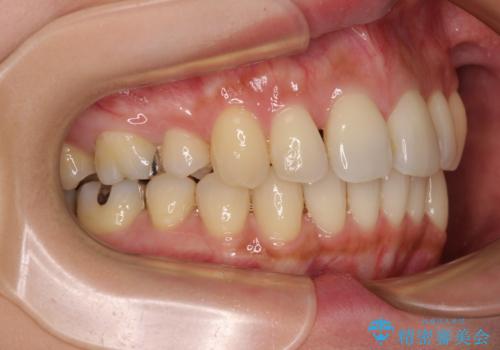

- 上の前歯の突出感を気にして来院された患者様です。

目立たない装置を希望とのことで、上顎左右第一小臼歯を抜歯し、インビザラインにて矯正治療を行うこととしました。

インビザラインにて抜歯矯正を行うと、高頻度で奥歯が咬み合わなくなります。

また、抜歯スペースに向けて奥歯が移動する際、必ず傾斜して移動するため、仕上がりの咬み合わせはワイヤー矯正と比べて明らかに劣ります。

抜歯スペースが閉じてからも咬みにくさ改善のためマウスピース矯正を継続するため、治療期間は長期化します。